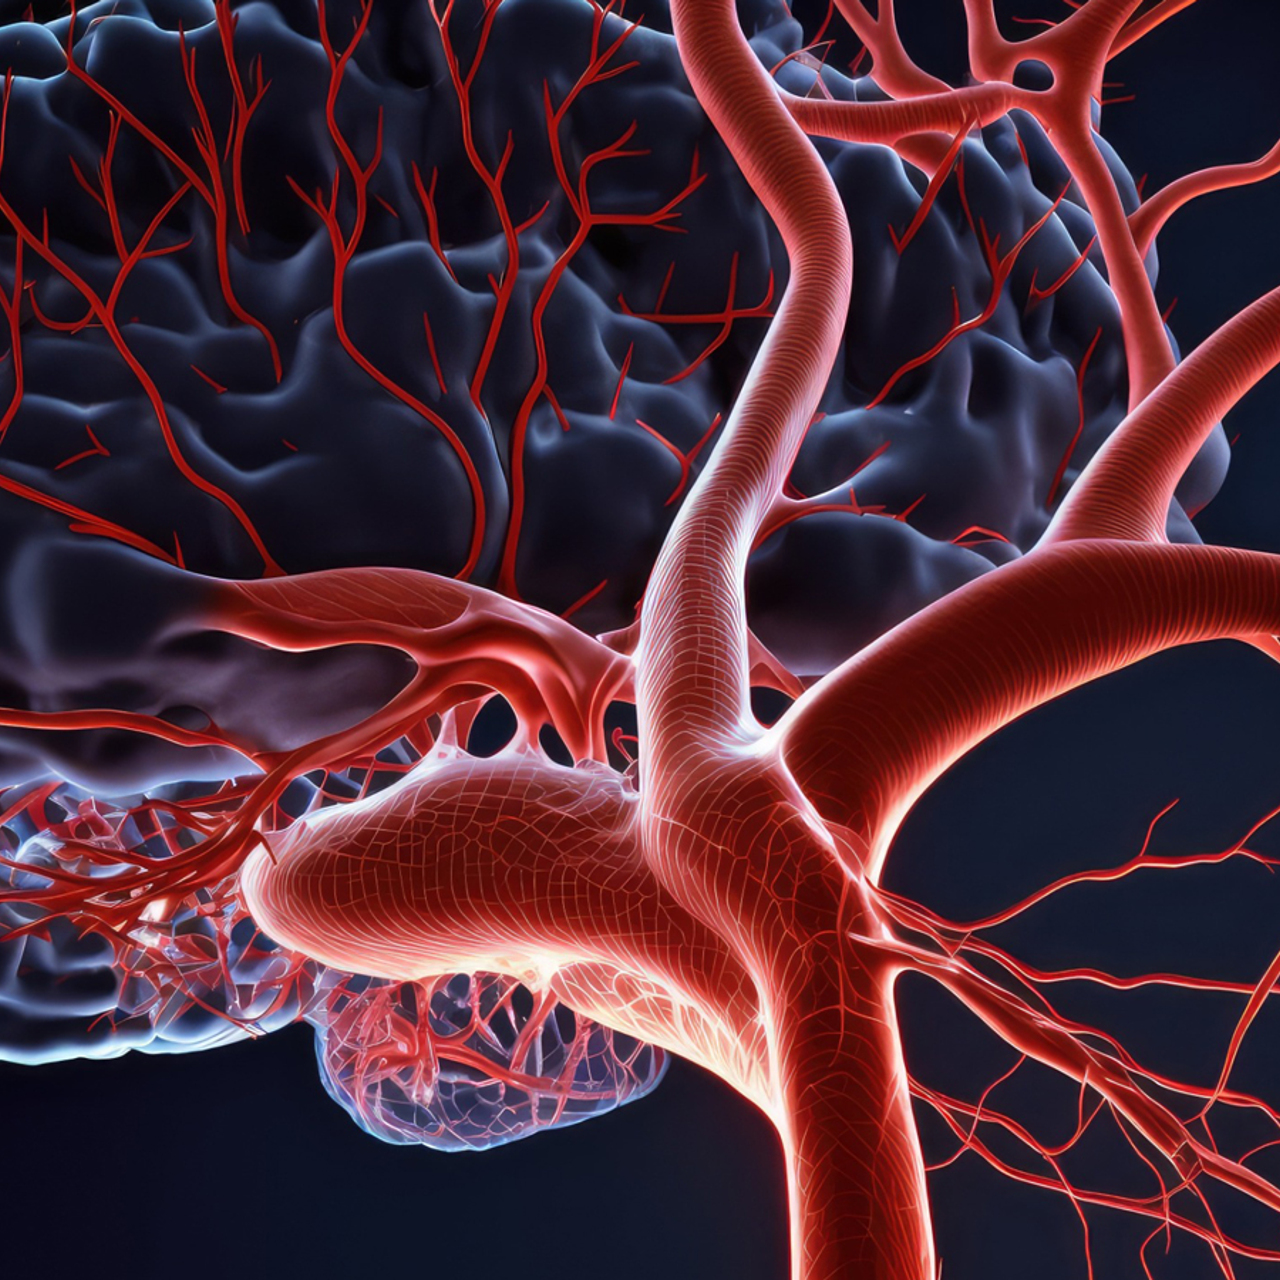

Снимки и иллюстрации микроаневризм сосудов головного мозга